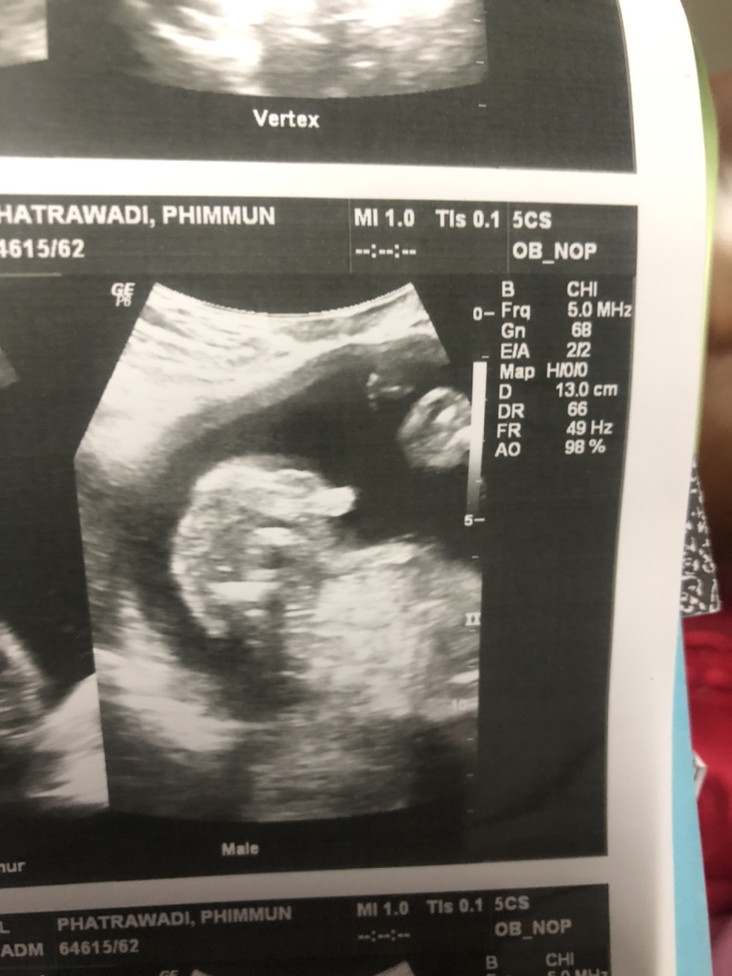

หมอเฟริมว่า เป็นเพศชาย แบบนี้มีอะไรผิดพลาดได้ไหมคะ

ชัดเจน ไม่น่าพลาดค่ะ

โอกาสพลาดน้อยมากค่า